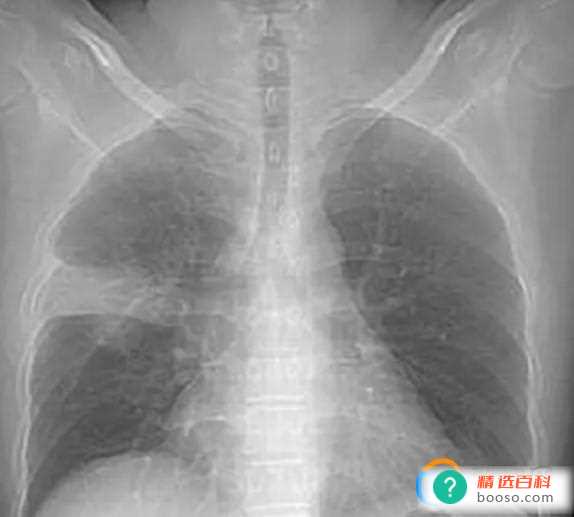

白肺意味着什么 严重吗

新冠发烧对肺有影响吗 会出现白肺吗